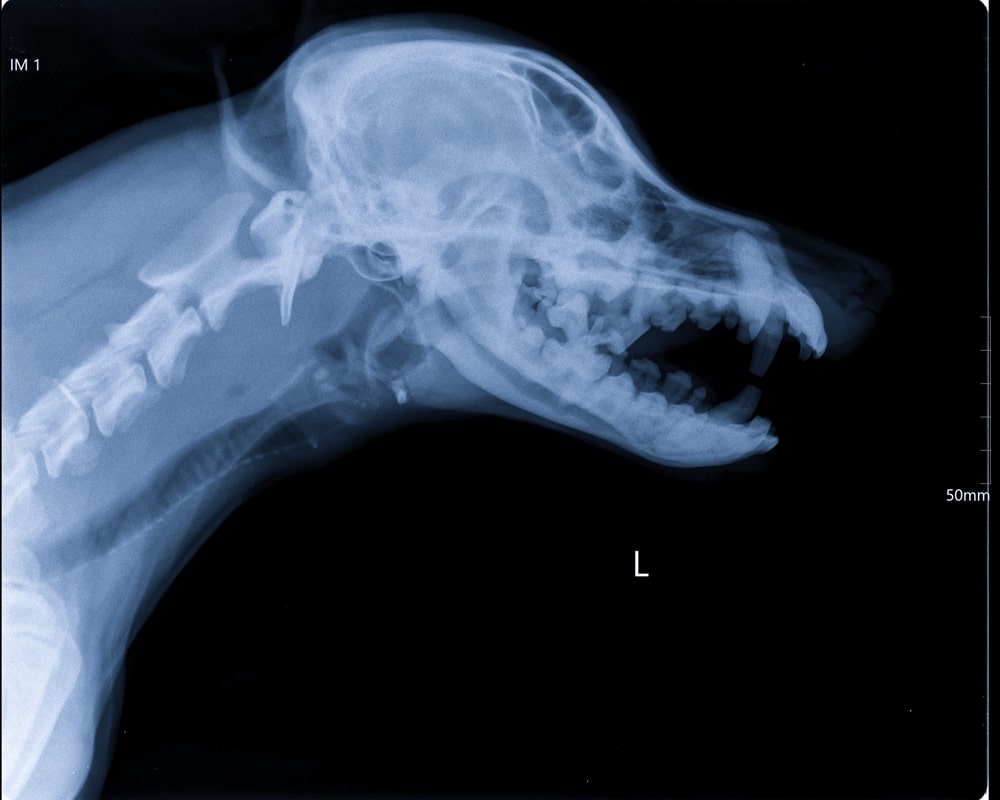

In my years of experience as a canine nutritionist, questions about dental health come up more often than you might expect. From worried owners noticing bad breath for the first time, to those dealing with a dog already showing signs of gum disease, oral health is clearly a concern that resonates, yet it’s one that often gets overlooked until a problem becomes hard to ignore.

That’s exactly why I wanted to put together this guide. Understanding what gingivitis is, why it develops, and what you can do about it can make a real difference to your dog’s comfort and long-term health. The good news is that with the right knowledge and a few consistent habits, it’s also one of the more preventable conditions we see in dogs.